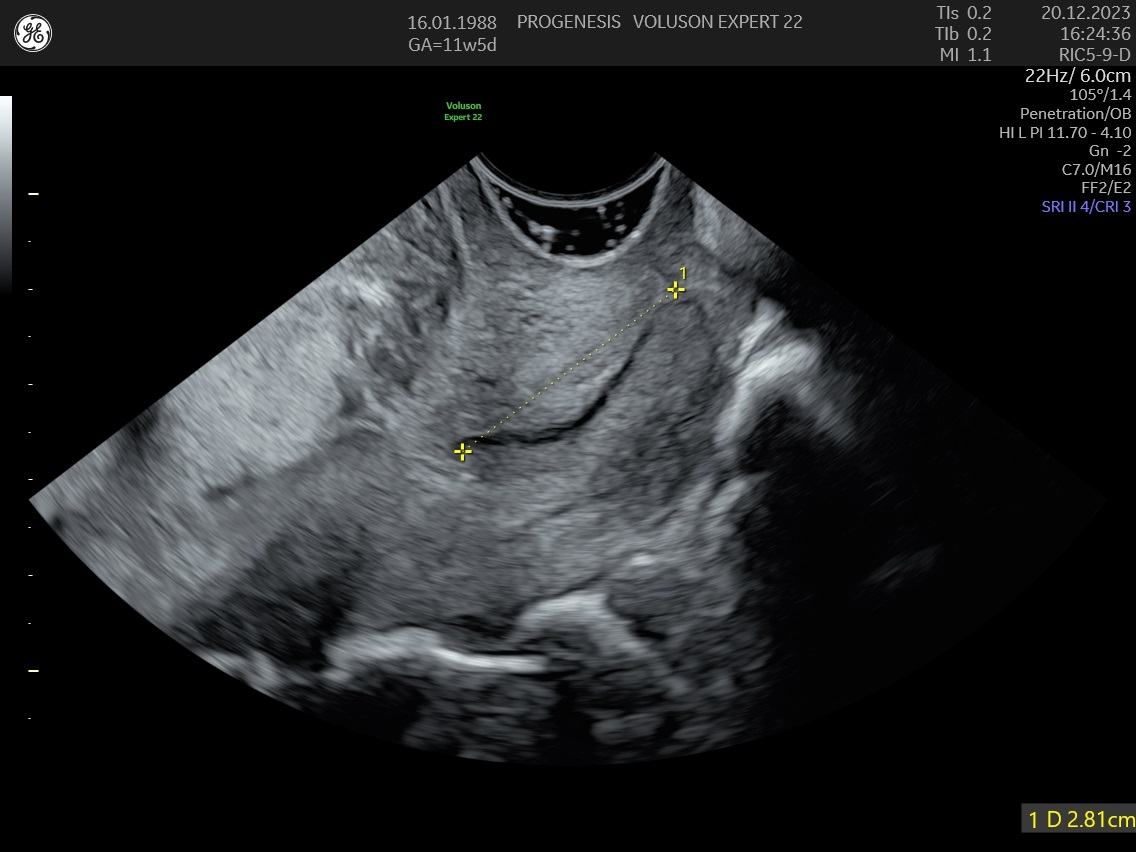

Το υπερηχογράφημα της αυχενικής διαφάνειας, πραγματοποιείται από τις 11 εβδομάδες +1 ημέρα έως 13 + 6 ημέρες κύησης και σε μήκος εμβρύου από 45mm έως 84mm.

Γίνεται συνήθως διακοιλιακά, ωστόσο σε αρκετές περιπτώσεις, για την ευκρινή απεικόνιση του εμβρύου, είναι αναγκαία και η διακολπική εξέταση.

.Κατά τη διάρκεια της κύησης ο τράχηλος της μήτρας πρέπει να είναι μακρύς και κλειστός.

Μετρώντας το μήκος του, υπολογίζουμε την πιθανότητα για πρόωρο τοκετό <34 εβδομάδες. Αξιολογείται σε όλες τις εγκύους, αλλά είναι ιδιαίτερα χρήσιμο στις μητέρες με παράγοντες κινδύνου όπως ιστορικό αποβολών 2ου τριμήνου ή πρόωρου τοκετού, πολύδυμη κύηση, συγγενείς ανωμαλίες μήτρας, ιστορικό επεμβάσεων τραχήλου (κωνοειδή εκτομή, LLETZ)